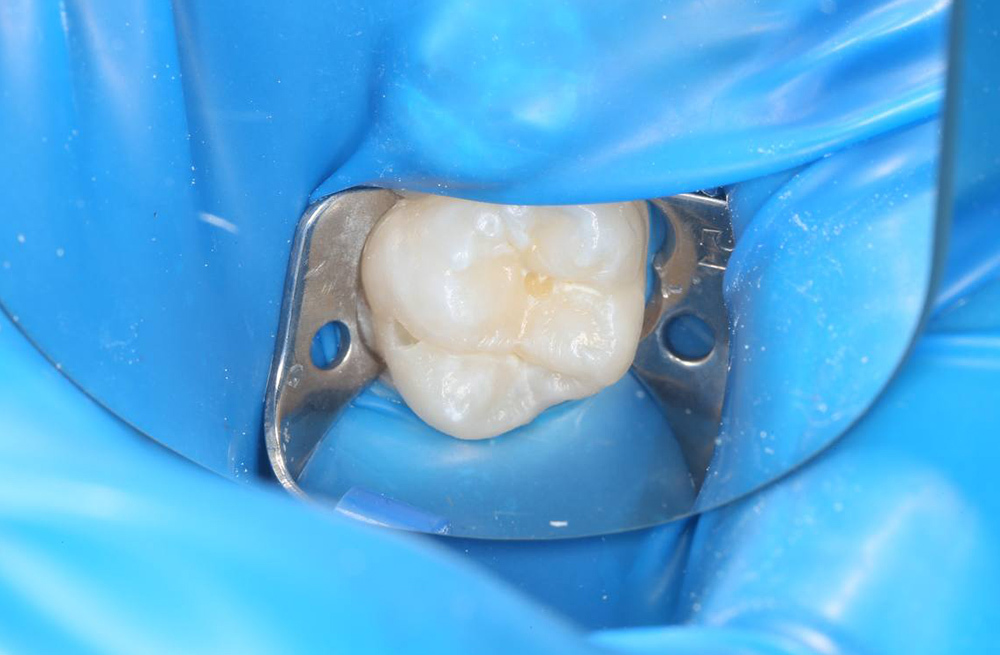

Лечение кариеса на жевательной поверхности постоянного зуба у подростка